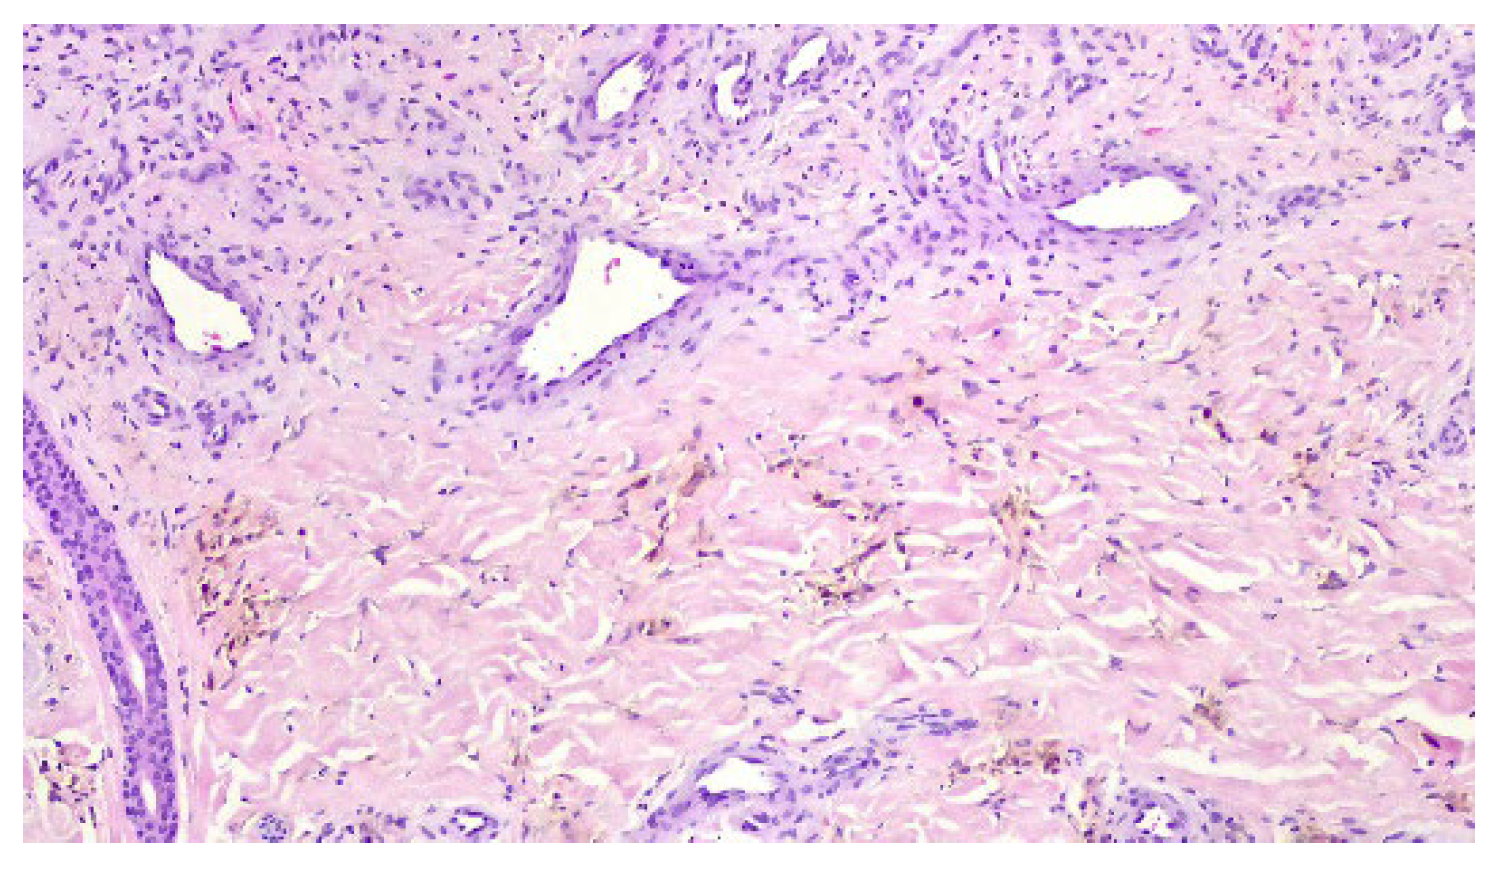

A punch biopsy was performed, and the histopathology disclosed moderate acanthosis, with focal spongiosis and small lymphocyte exocytosis. In the upper dermis, a marked neovascularization, composed of lobules of thick-walled capillaries, was observed in association with erythrocyte extravasation and hemosiderin deposition (Figure 3 and Figure 4). Immunochemistry for HHV-8 was negative (Figure 5). The clinicopathological correlation led to the diagnosis of AAD due to a venous malformation. This case illustrates a possible pathophysiological overlap with the venous malformation contributing to venous insufficiency.

Figure 3. Moderate acanthosis with focal spongiosis, associated with a marked neovascularization in the upper dermis, erythrocyte extravasation, and hemosiderin deposition.